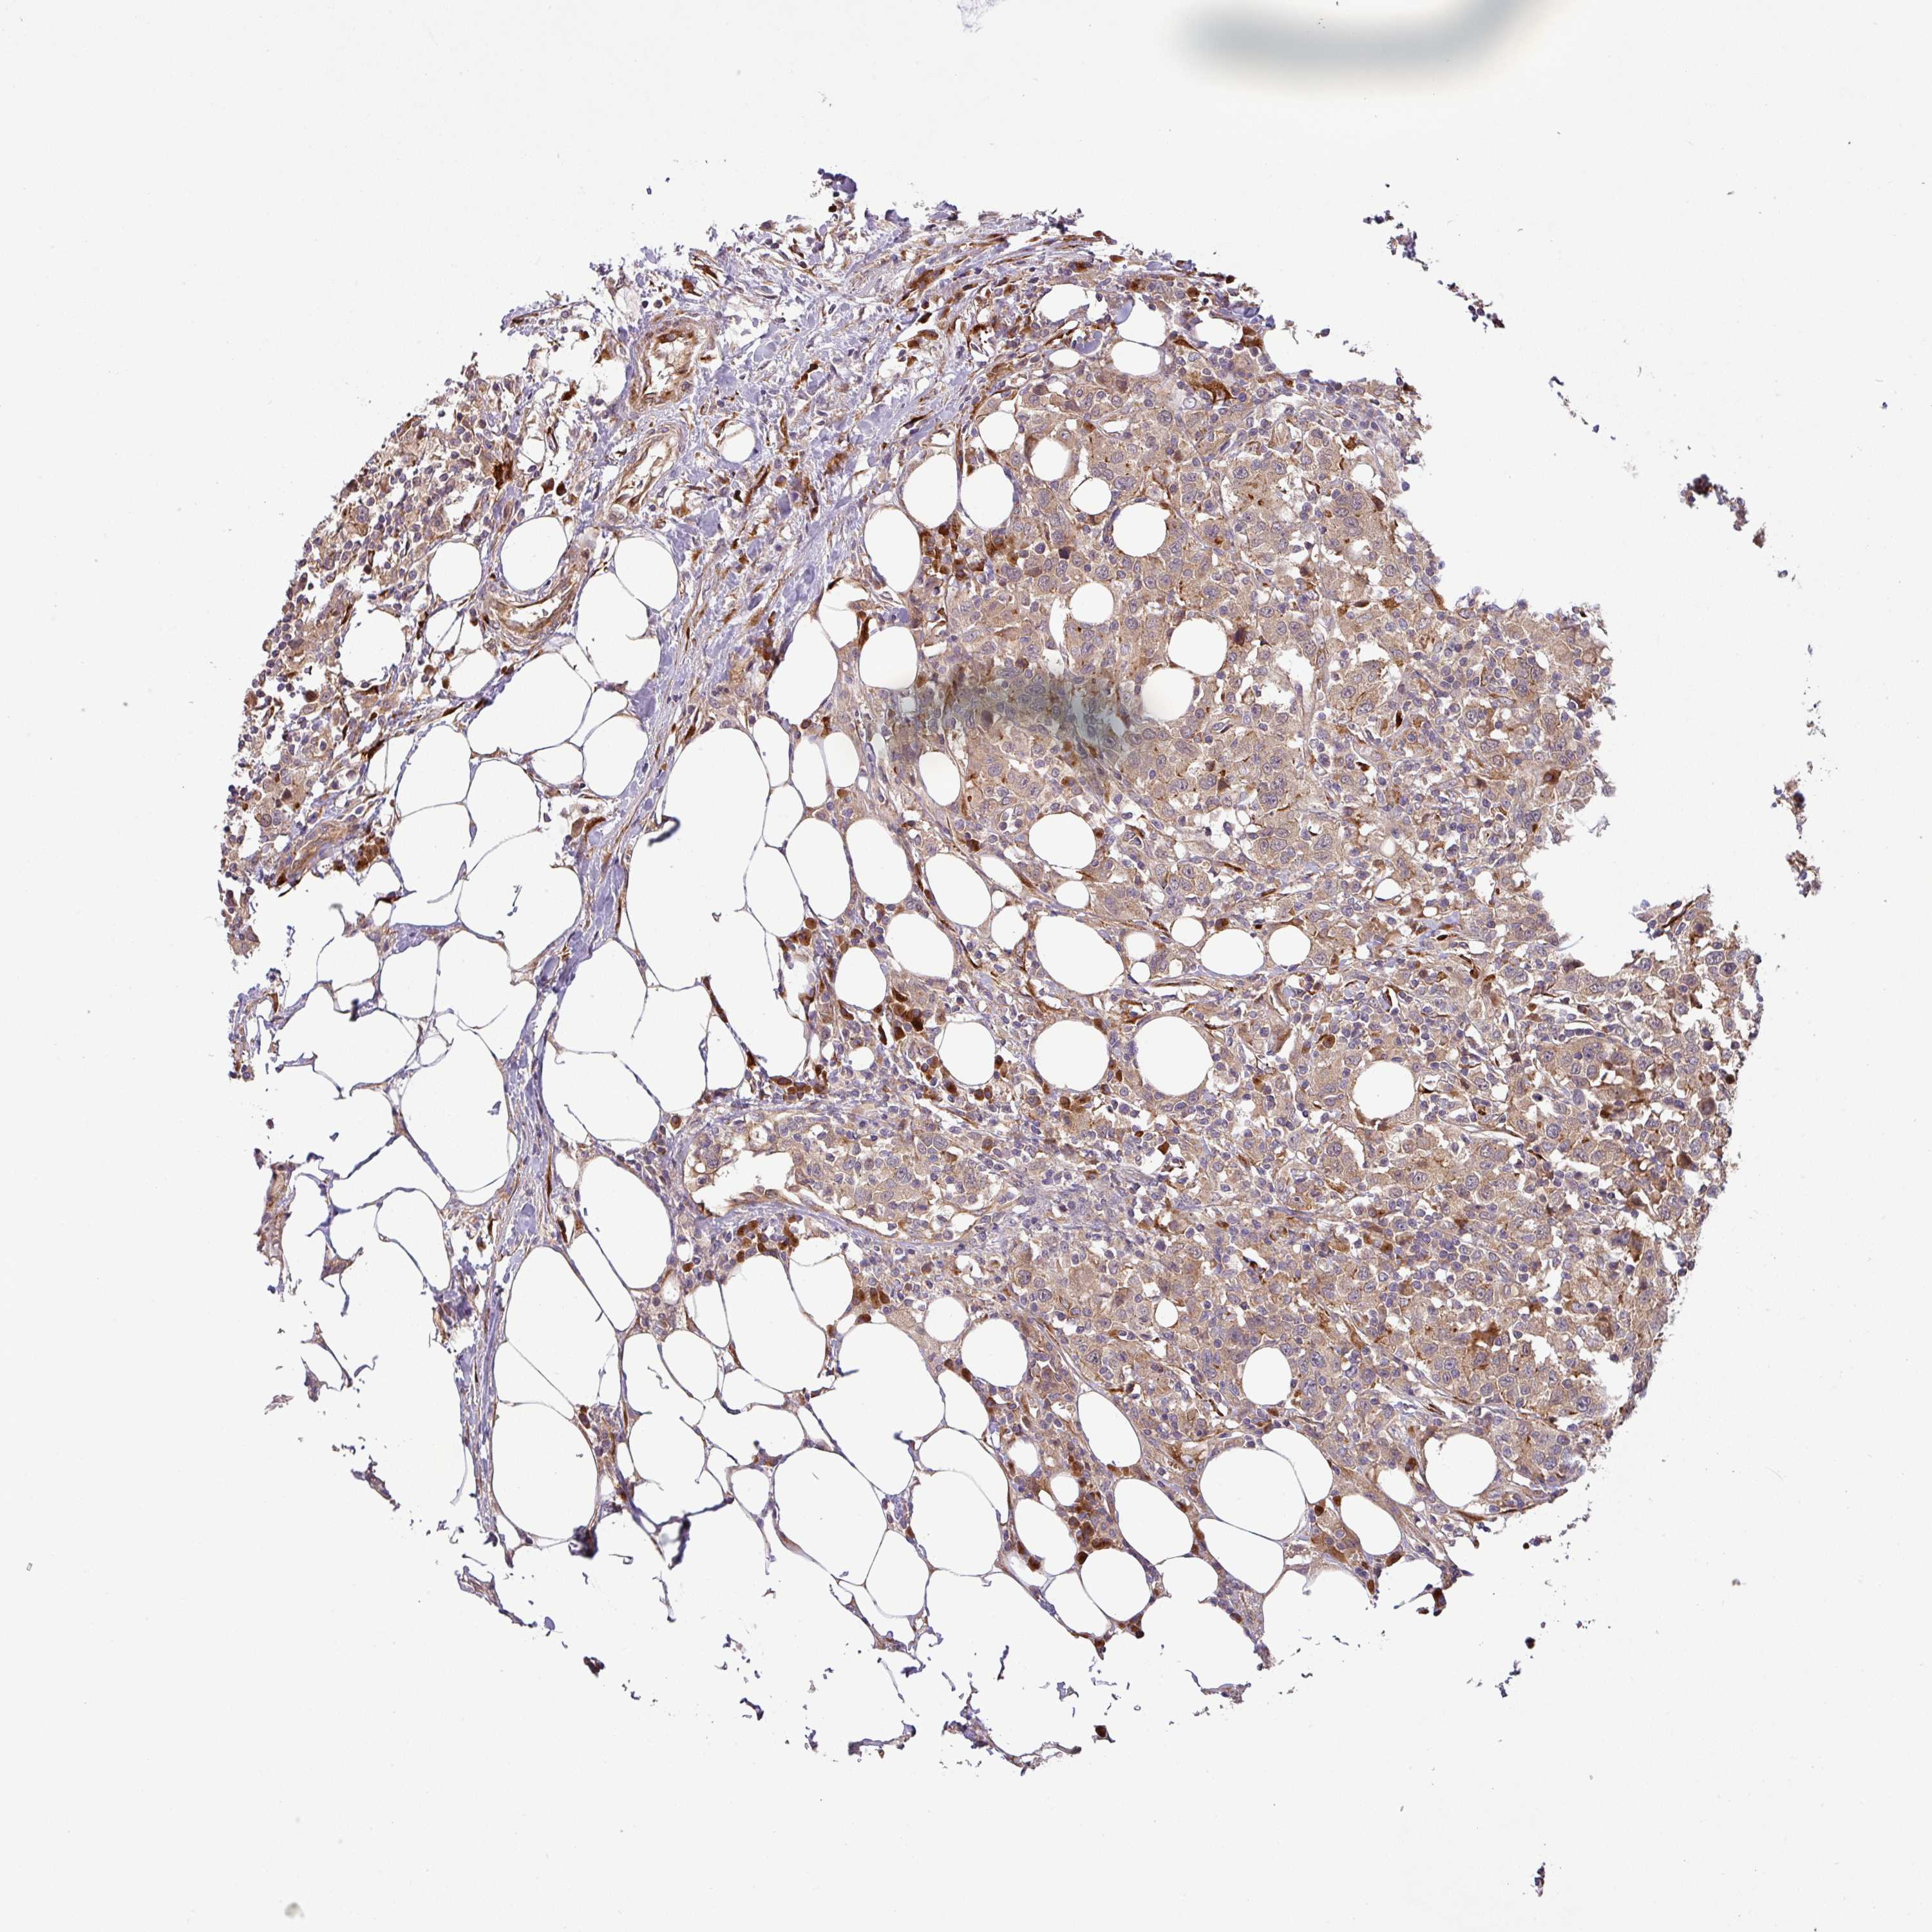

UROTHELIAL CANCER - Protein expressioni

A mouse-over function shows sample information and annotation data. Click on an image to view it in a full screen mode. Samples can be filtered based on level of antibody staining by selecting one or several of the following categories: high, medium, low and not detected. The assay and annotation is described here.

Note that samples used for immunohistochemistry by the Human Protein Atlas do not correspond to samples in the TCGA dataset.

Antibody stainingi

Antibody staining in the annotated cell types in the current human tissue is reported as not detected, low, medium, or high, based on conventional immunohistochemistry profiling in selected tissues. This score is based on the combination of the staining intensity and fraction of stained cells.

Each image is clickable and will lead to virtual microscopy that enables deeper exploration of all samples and also displays staining intensity scores, fraction scores and subcellular localization as well as patient and tissue information for each sample.

Antibody HPA051148

Staining

High

Medium

Low

Not detected

Intensity

Strong

Moderate

Weak

Negative

Quantity

>75%

75%-25%

<25%

None

Location

Nuclear

Cytoplasmic/membranous

Cytoplasmic/membranous,nuclear

Urothelial carcinoma, High grade

Urothelial carcinoma, Low grade